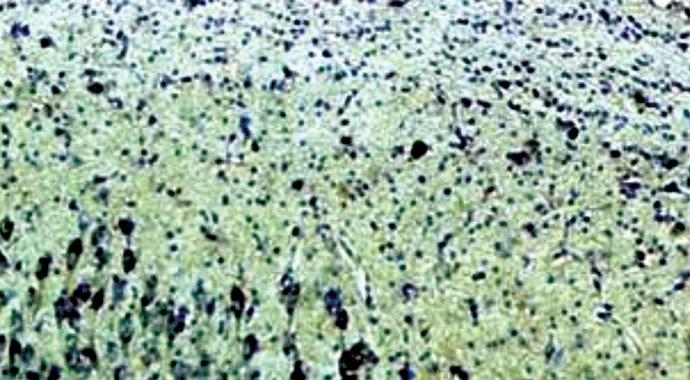

Subsequent studies further suggested an angiogenic response to chronic hydrocephalus. Hypoxia, an established trigger for angiogenesis, was observed. CSF oxygen saturation was lower in chronic hydrocephalus, improved with shunting and decreased again with shunt removal.2 Receptors for vasoactive endothelial growth factor (VEGF), a promoter of angiogenesis, increase in the hydrocephalic hippocampus and caudate (Figure 2)3,4 and decrease with shunting. Finally, VEGF levels are measurable in human and animal CSF and are elevated in hydrocephalus.5 In many but not all cases, increased VEGF receptor densities correlated with increased density of capillaries.

Figure 2. Photomicrographs showing increased expression of the VEGFR-2+ receptor in the hippocampal CA2/3 region in canine chronic hydrocephalus (left) relative to surgical control (right). Reprinted from Neuroscience (Dombrowski et al4), ©2008 Elsevier BV.